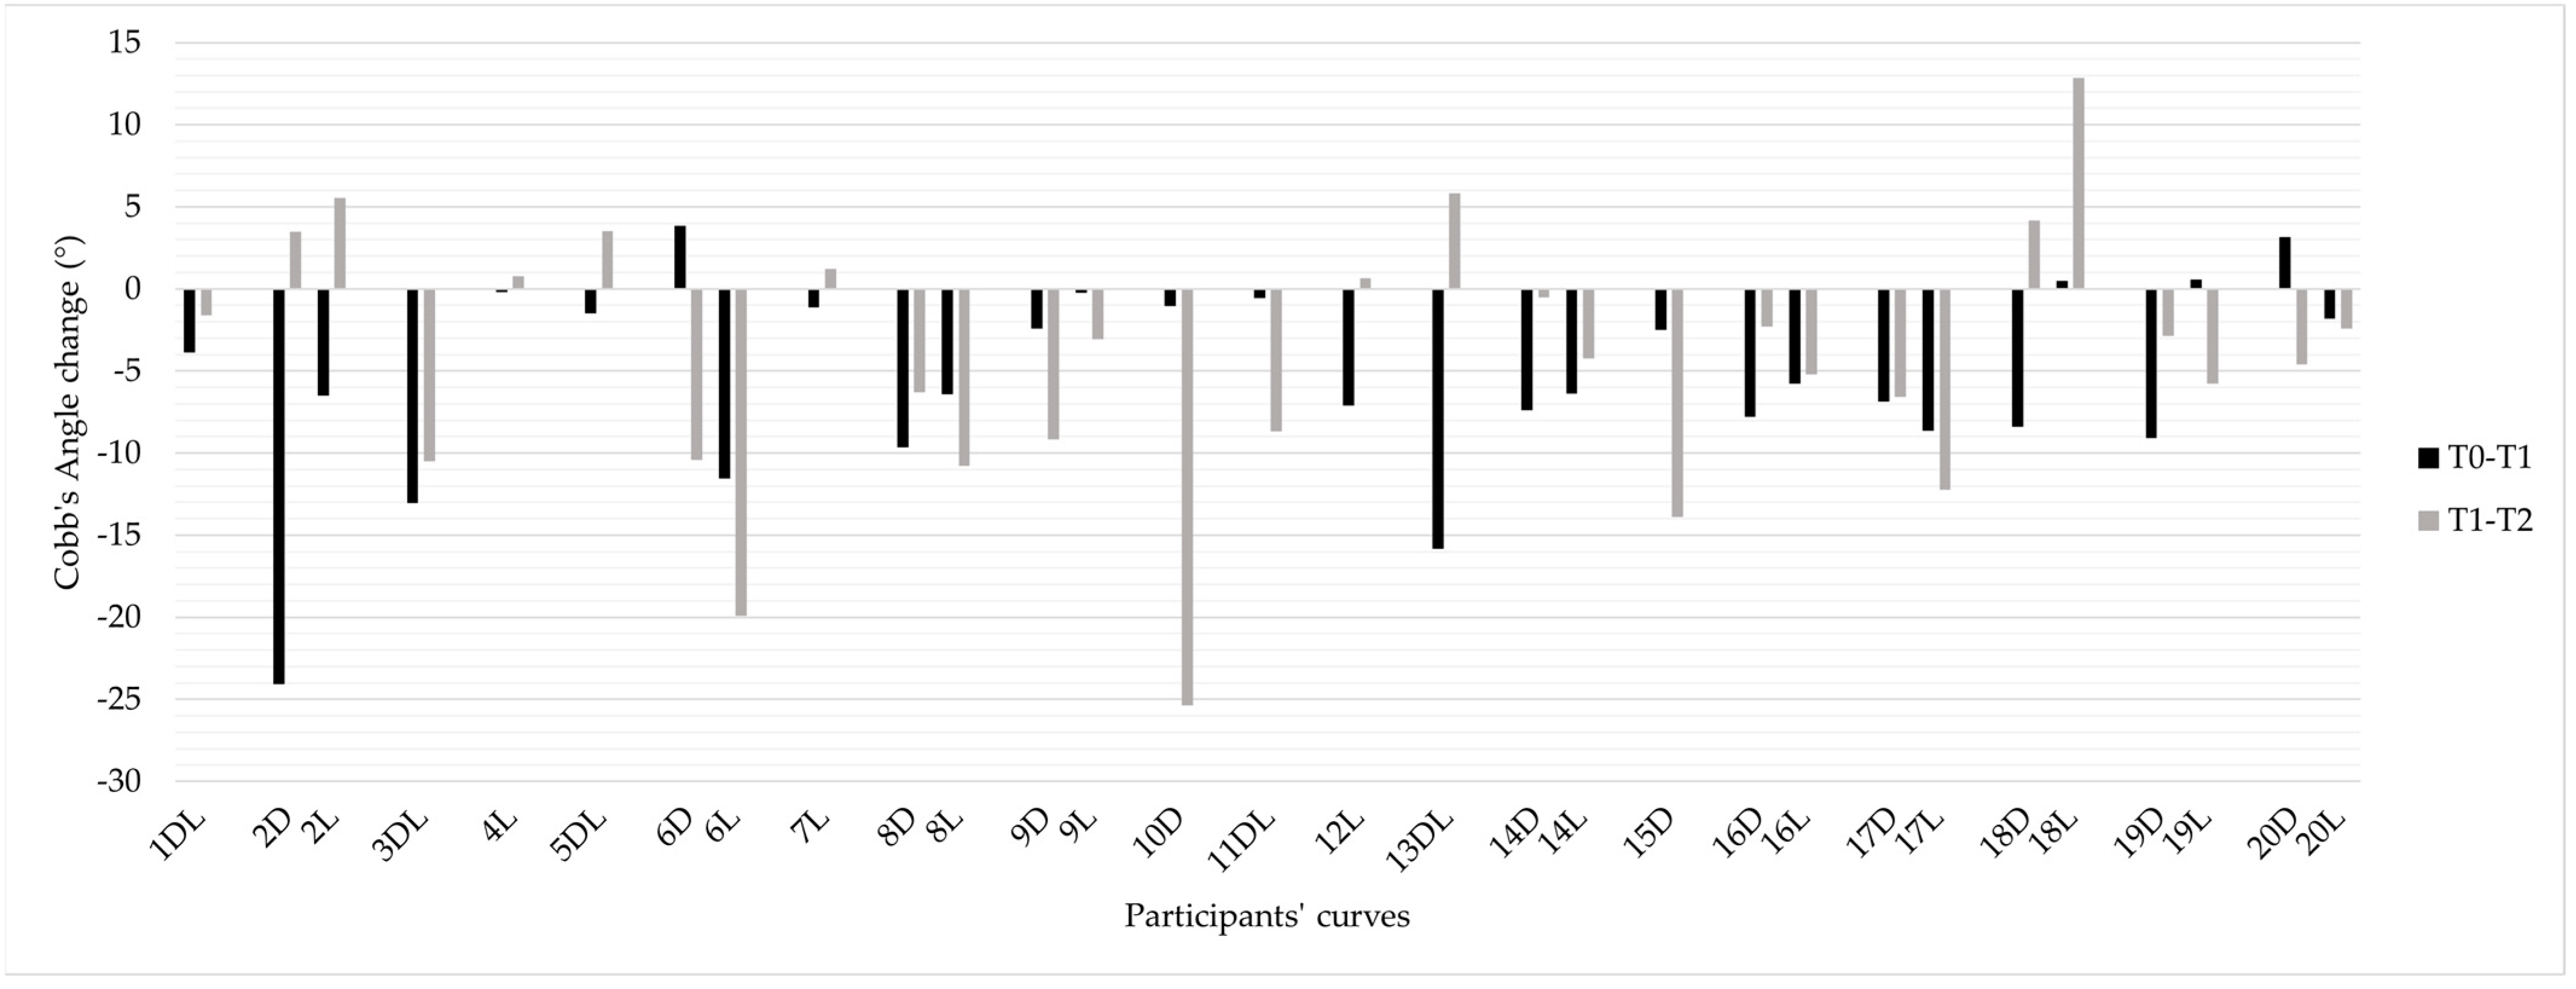

3.1. Scoliosis Characteristics and Progression

3.2. Individual Responses to Intervention

4.1. Effect of the HEP on Scoliosis Progression